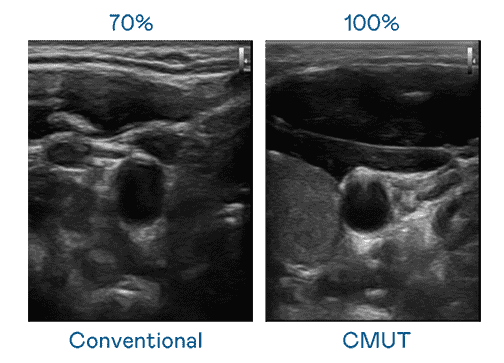

CMUT 技术是一种用电容式微机电元件来产生超音波讯号的技术。。。与传统 PZT 压电式技术相比,,CMUT 频宽增加 30%,,,更宽频的超音波讯号让影像解析度大幅提升,,是实现高影像品质医疗超音波扫描、、促进精准医疗发展的关键技术。。

大频宽带来超清晰影像

超音波影像的解析度高低,,首先取决于探头能发出的讯号频宽。。。。Wepay CMUT 可提供高清晰的超音波讯号,,提供高频宽、、、、高灵敏度、、、影像纹理细节更高的超音波影像,,协助医护人员缩短影像判读时间及利用精准的医疗影像进行诊断。。